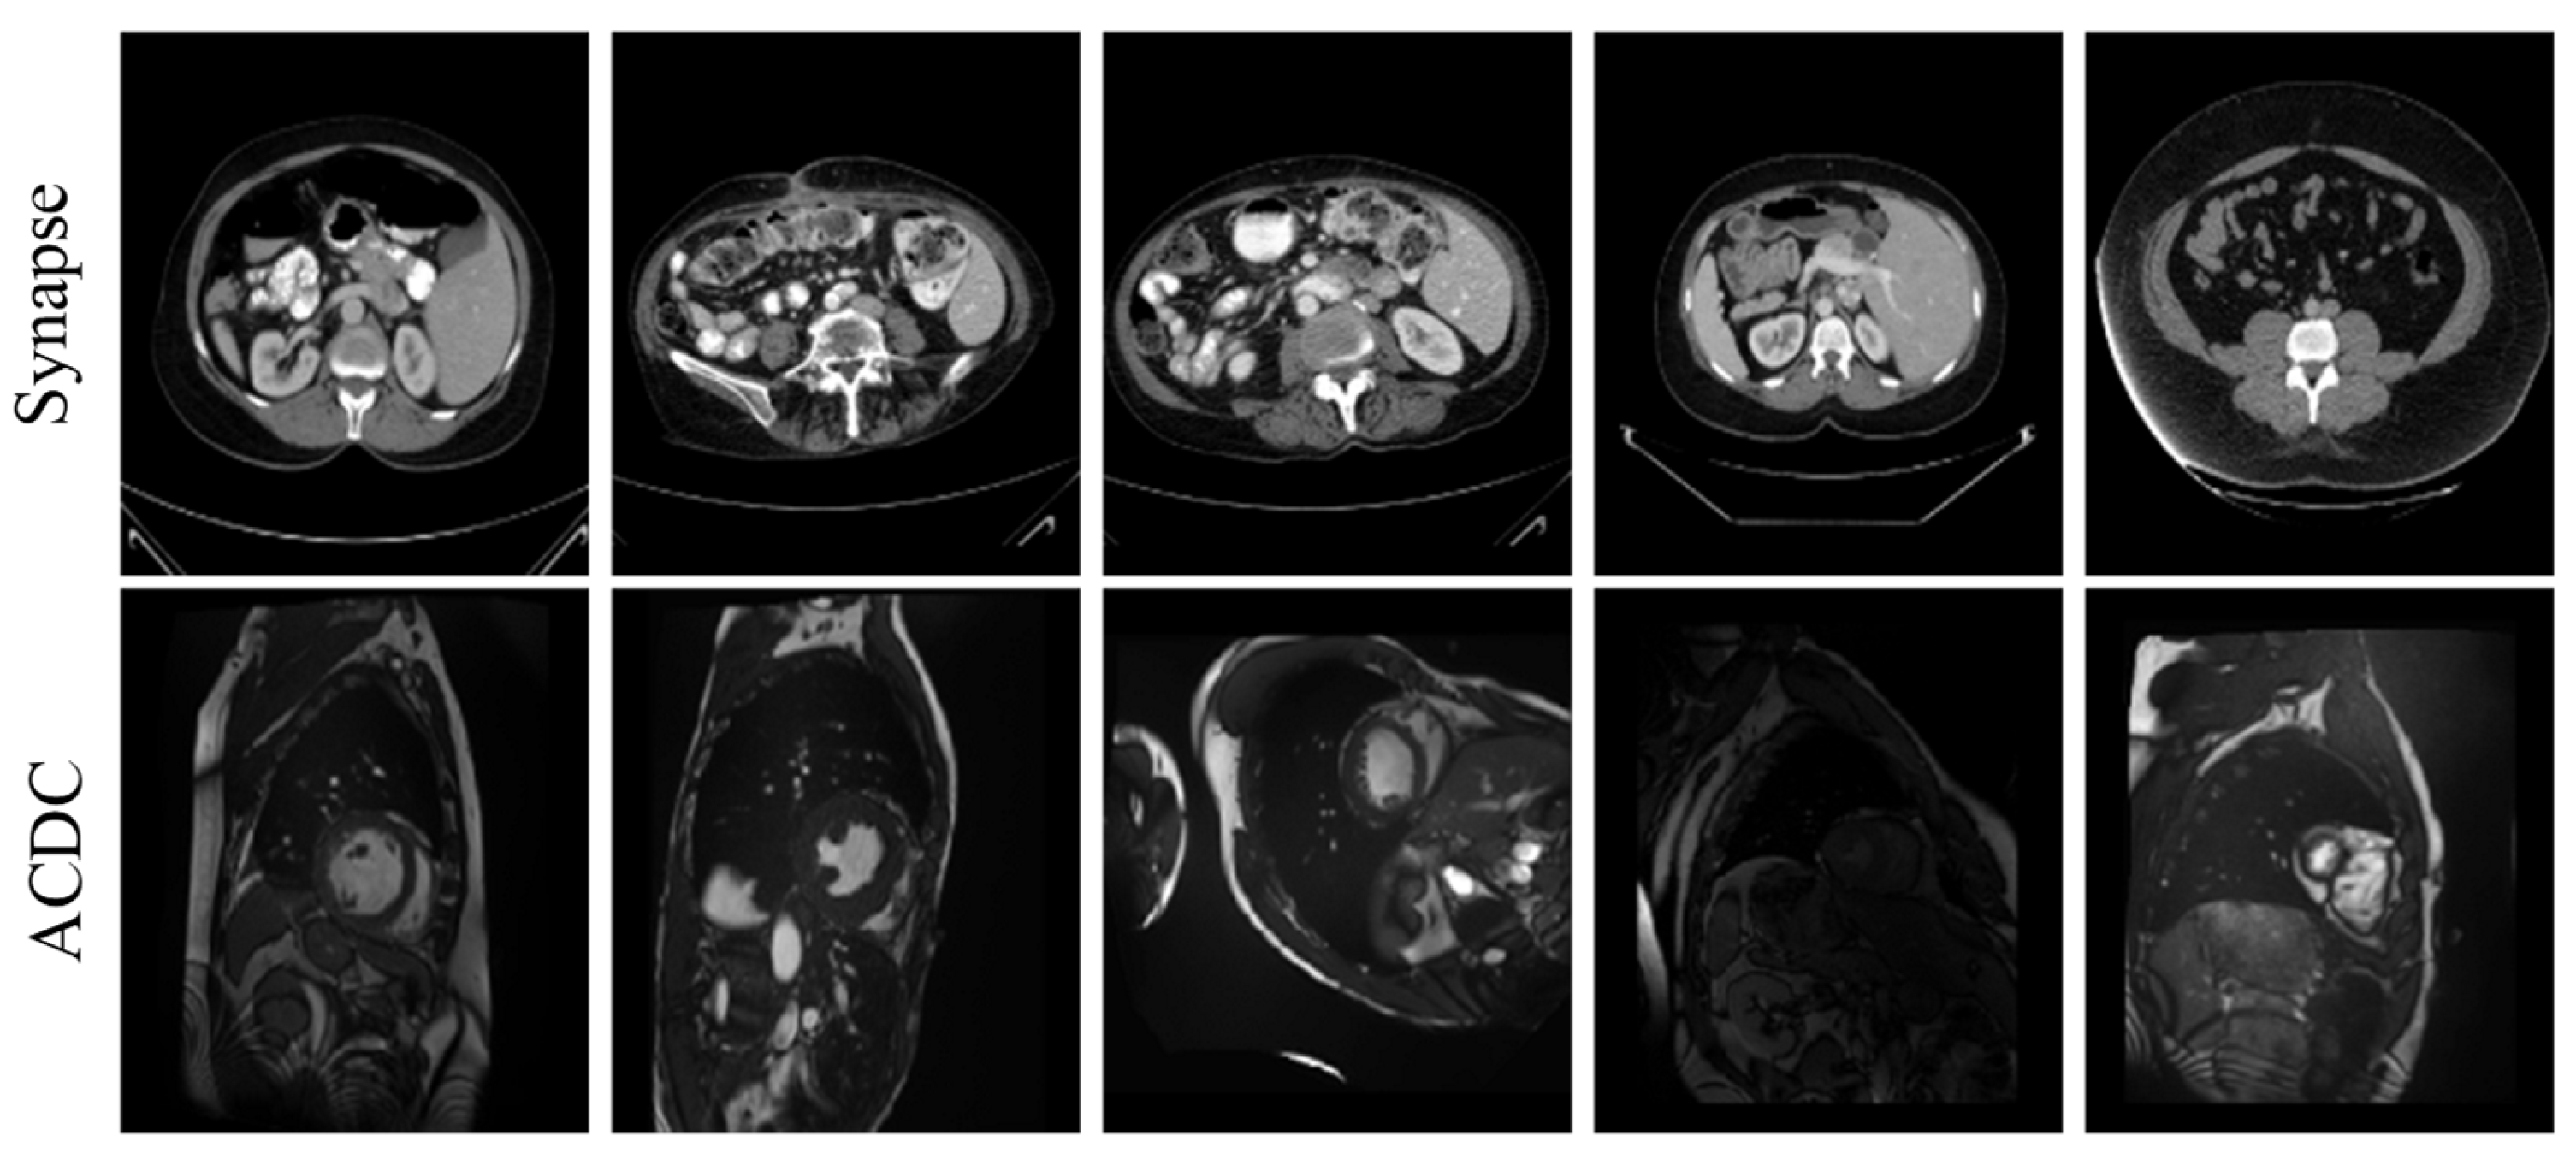

4.3.2. Qualitative Experimental Analysis

To further validate the segmentation performance of BFLE-Net, this section presents a systematic visualization and comparison experiment conducted on the Synapse and ACDC datasets. By visualizing the segmentation results, the advantages of BFLE-Net in handling complex anatomical structures are thoroughly analyzed.

In this study, the performance of various segmentation methods, including U-Net, MT-UNet, TransUNet, and BFLE-Net, is systematically compared on the Synapse and ACDC datasets. The experimental results reveal significant performance differences among the methods in segmenting complex anatomical structures. As shown in Figure 6, in the multi-organ segmentation task on the Synapse dataset, both U-Net and MT-UNet suffer from considerable over-segmentation, particularly in the stomach region, where organ misclassification occurs. More notably, MT-UNet and TransUNet exhibit substantial topology confusion in the segmentation of the left and right kidneys, as well as inaccuracies in localizing the spatial relationship between the gallbladder and the liver. These issues highlight that current methods still face significant challenges in incorporating anatomical prior knowledge and modeling 3D spatial context dependencies for multiple organs. In contrast, the method proposed in this study substantially improves the completeness of segmentation and effectively addresses the problem of semantic confusion between organs, particularly in distinguishing neighboring organs (e.g., the liver and gallbladder) with similar grayscale features, thus demonstrating significant advantages.

Figure 6. Qualitative analysis results on the Synapse dataset. Note: The green box in the figure indicates the location where the effect of segmentation is insufficient.

Electronics 14 03054 g006